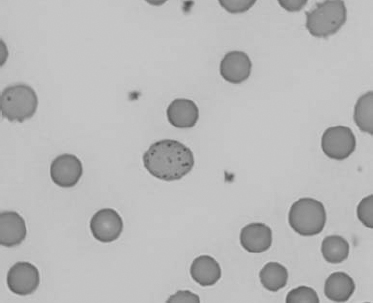

See Figs 1.3–1.24 for pictures of various types of RBC morphology.

Figure 1.16 Feline blood film showing Mycoplasma hemofelis organisms (hemobartonellosis). Organisms are not always visible in blood smears from infected cats (also see color section).